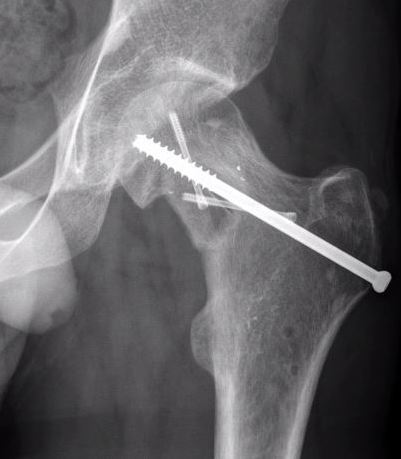

Xray

Shallow cortical defect on the surface of long bones

Periosteal chondromaXray periosteal chondroma